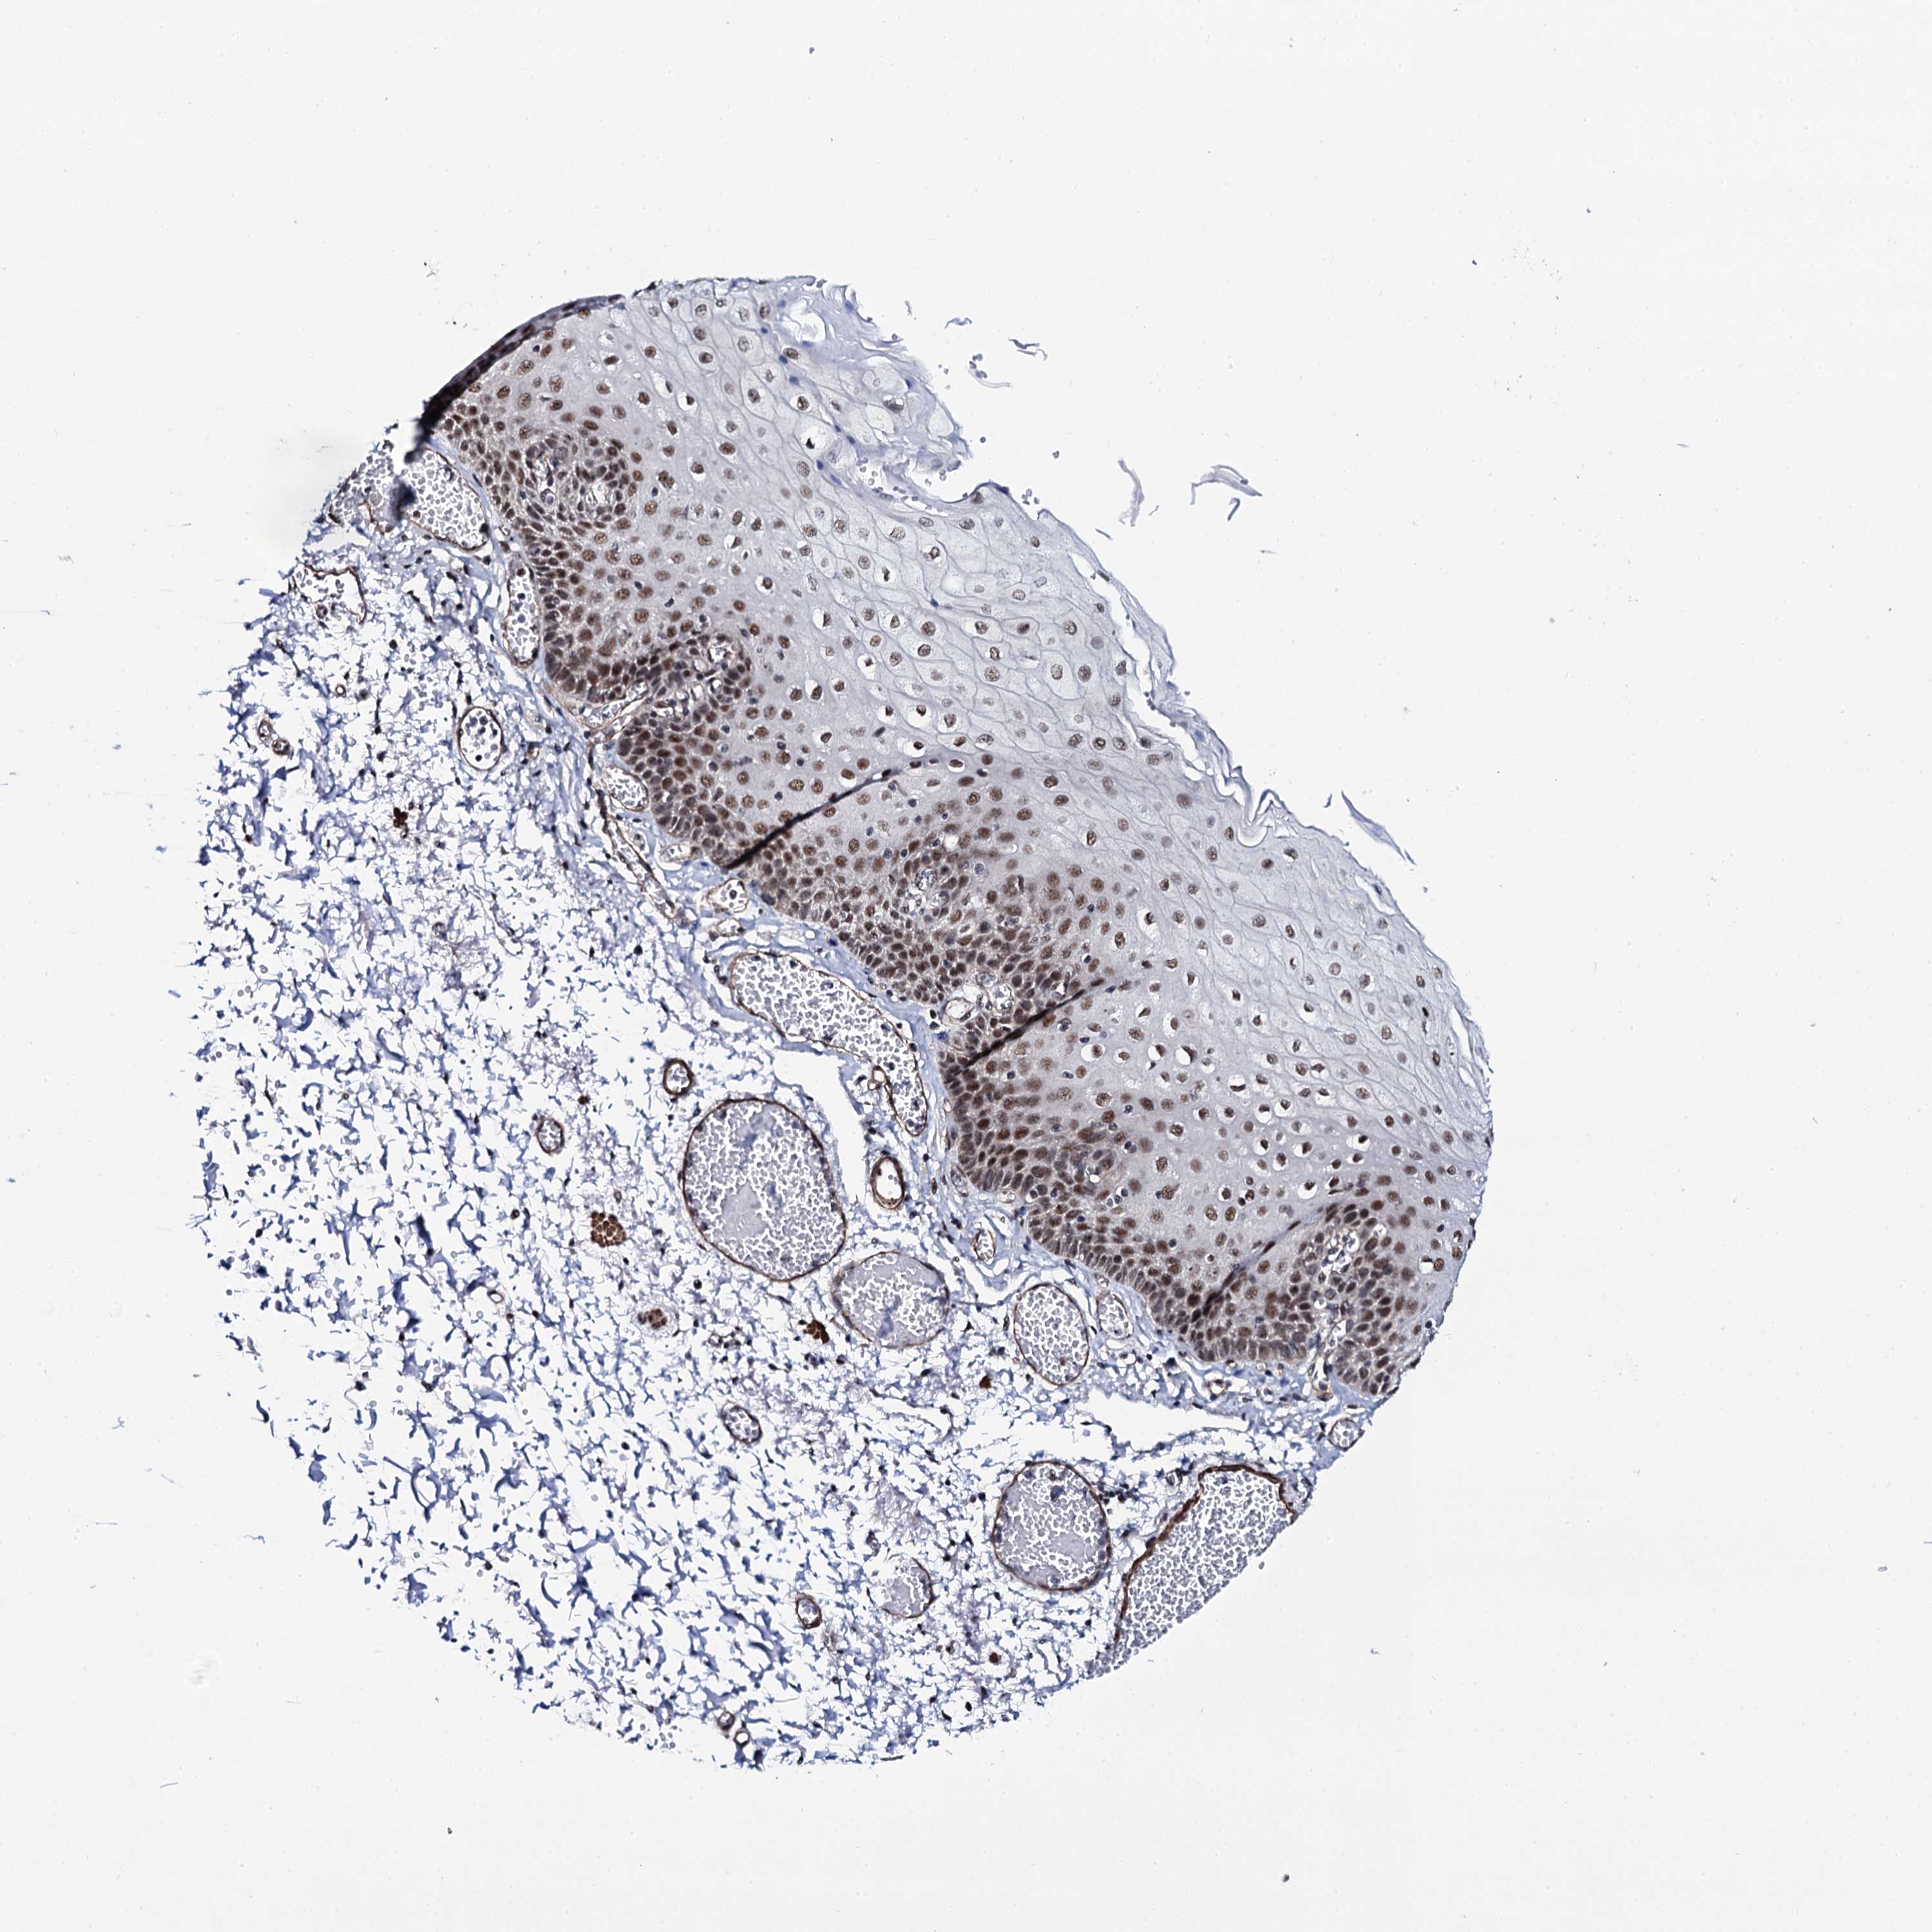

ESOPHAGUS - Antibody stainingi

Antibody staining in the annotated cell types in the current human tissue is reported as not detected, low, medium, or high, based on conventional immunohistochemistry profiling in selected tissues. This score is based on the combination of the staining intensity and fraction of stained cells.

Each image is clickable and will lead to virtual microscopy that enables deeper exploration of all samples and also displays staining intensity scores, fraction scores and subcellular localization as well as patient and tissue information for each sample.

Antibody HPA039878

Squamous epithelial cells Medium